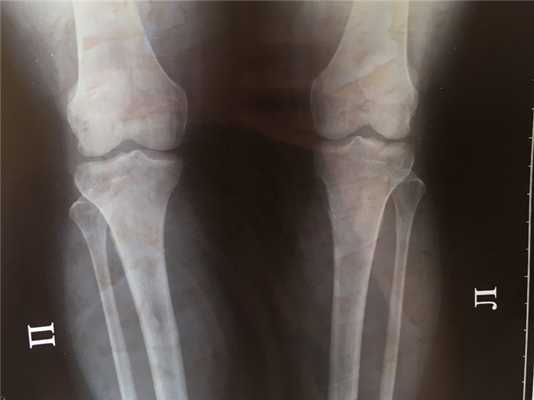

Крупная остеохондрома проксимальной части малоберцовой кости: рентгенограмма (а), трехмерная КТ-реконструкция (б), КТ-срез (в). Образования этой локализации могут стать причиной нейропатии малоберцового нерва.

В данном случае имеется выраженная вогнутая деформация прилежащего кортикального слоя большеберцовой кости, являющаяся примером вторичной деформации кости вследствие экспансивного роста остеохондромы. Остеохондрома на ножке дистального отдела бедра. Образования обычно растут в противоположную от суставов сторону. Спонгиозная часть остеохондромы сообщается с костно-мозговым каналом пораженной кости. Образование сохраняет единство кортикального и спонгиозного слоя с материнской костью, что является рентгенологическим признаком остеохондромы. Остеохондрома на широком основании дистального конца большеберцовой кости. Обратите внимание на угловую деформацию пилона большеберцовой кости. Образования подобной локализации могут приводить к нарушению роста и угловой деформации костей. Множественный остеохондроматоз, сопровождающийся деформацией костей. Это наследственное заболевание с аутосомно-доминантным типом наследования. Пациент с симптоматикой, обусловленной компрессией большеберцового нерва. Рентгенограмма коленного сустава пациента с множественными остеохондромами. Имеются множественные поражения дистального отдела бедра и проксимального отдела большеберцовой кости и сопутствующая деформация конечности. Интраоперационная картина остеохондромы. Обратите внимание на непрерывность кортикального слоя и «шапку», образованную зрелой хрящевой тканью. Микропрепарат остеохондромы. Гистологически эти образования выглядят также, как зоны роста костей — хрящевая ткань, созревающая путем энхондрального окостенения и превращающаяся в нормальную костную ткань. Макропрепарат остеохондромы. Обратите внимание на хрящевую «шапку» с сохранением непрерывности костно-мозгового пространства остеохондромы и пораженной кости.